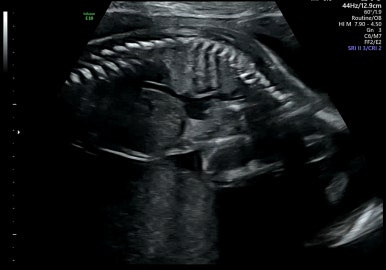

21주 1일

정밀초음파로 외형, 장기 등이 이상이 없는지 확인하는 시기이다.

머리부터 발끝까지 꼼꼼하게 검사를 하게 된다!

손발 등 너무 정교하게 생겨서 너무 신기하다!